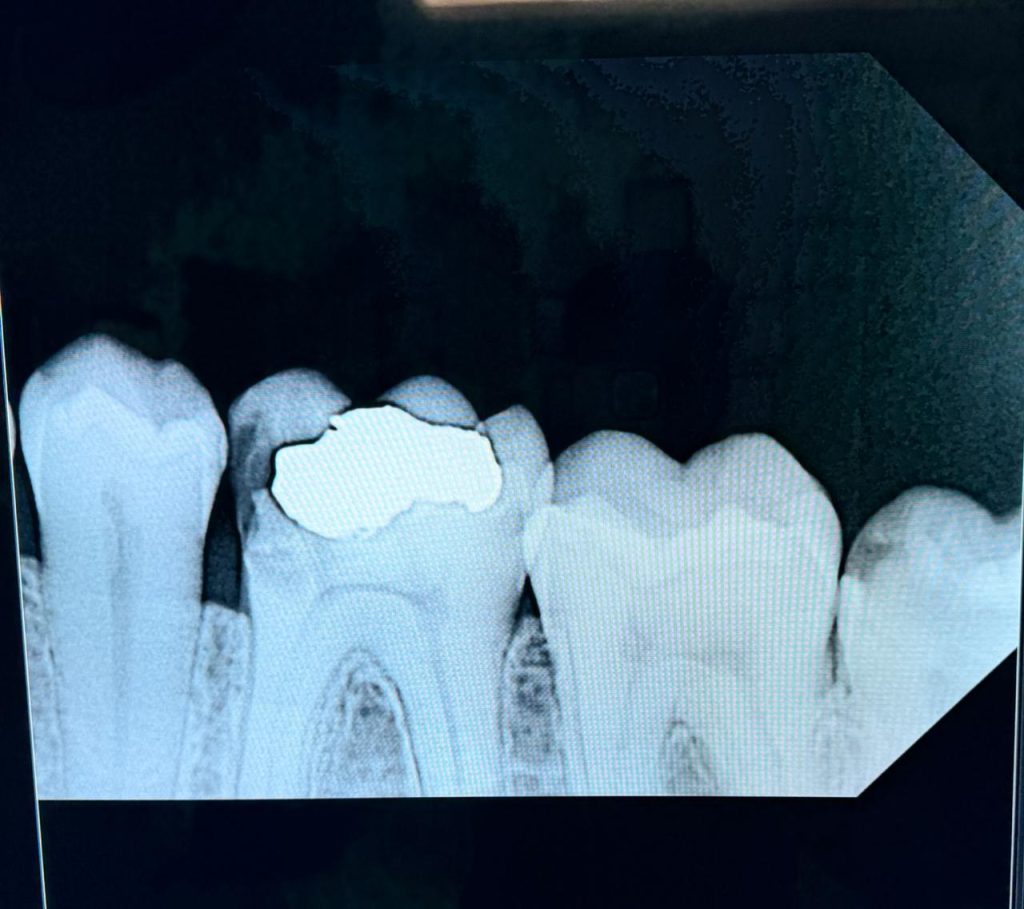

The patient presented with a distal carious lesion on a partially infra-occluded mandibular third molar exhibiting food impaction and sensitivity (Fig 1). CBCT and radiographs confirmed a deep Class II lesion extending sub-gingivally, but with adequate periodontal attachment for isolation and restoration.

- Fig 1: Pre-operative view showing distal caries on infra-occluded third molar.